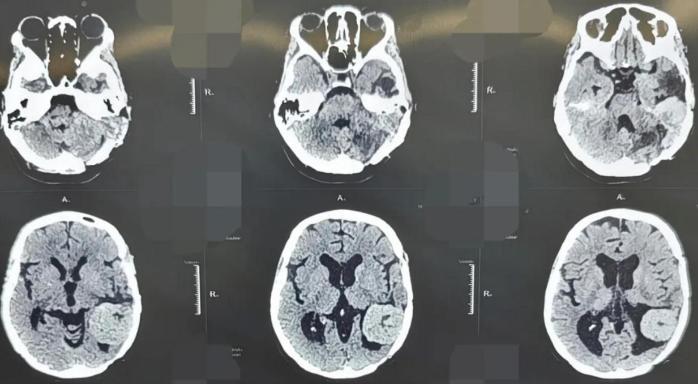

术前头部CT检查。

45岁的患者张女士,因“头晕、耳鸣伴听力下降”来到西安市红会医院就诊。她曾在2011年和2017年两次因颅内血管周细胞瘤于外院接受开颅手术治疗,并进行术后放化疗。此次入院后影像学检查显示,肿瘤在左侧颞部及桥小脑角区复发。该区域毗邻脑干、面神经、听神经及多条重要血管,素有“生命禁区”之称,手术风险极高。